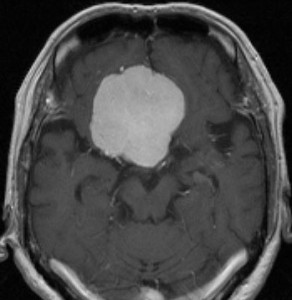

大脳鎌テント接合部髄膜腫 falcotentorial meningioma

30代の女性に発生した髄膜腫です,一見すると松果体細胞腫と見分けはつきません。右の画像に見られるように典型的な中脳水道狭窄を生じていました。

軽度の閉塞性水頭症もありますが,頭痛も無く無症状なので経過を観察しました。髄膜腫だと診断できるのは,右の画像で見られるようにガレン大静脈が右側に偏っているからです。松果体細胞腫の場合は,ガレン大静脈は上方に変位します。

1年間経過観察したら水頭症が進行して脳室が拡大,腫瘍のサイズも大きくなりました。右側の画像で見られるようにガレン大静脈の左側のテントの下面から発生した髄膜腫でした。

左は手術直後の画像です,手術は左側のテント下面を見るために,後頭部経テント法 OTA occipital transtentorial approach で,小脳テントの左側を切断して腫瘍を全摘出しました。右側は6年後の画像ですが,腫瘍再発はありません。

「注意」症状のない患者さんには,なかなか勧められないリスクの高い手術です。この患者さんの場合は無症状で水頭症も軽度で経過観察をしたのですが,本当はそうしてはならないものでした。閉塞性水頭症が急激に悪化して,急性水頭症のために意識障害になる可能性があるものです。